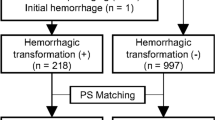

Figure 1 depicts the study flowchart. The baseline data of the enrolled cases in both training and validation cohorts are summarized in Table 1. We also investigated the differences in baseline features between the good and poor functional outcome groups in both training and validation cohorts. Marked differences were found in age, infarct volume, NIHSSbaseline, NIHSS24h, and hemorrhage (all p < 0.05).